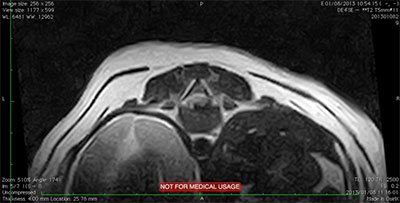

主訴:一昨日から右後足の動きがおかしく、昨日から両後足が全く動かなくなったとのことで来院されました。 診察時も両後足完全麻痺で、さらに大変なことに足の小指を刺激して痛みがあるがどうかを確認する深部痛覚が消失しており、早く治療しないと一生歩けなくなるかもしれない状態でした。飼い主様とご相談して、まずMRI検査にて脊髄の状態を確認後、手術可能であれば手術を行うことで治療をすすめました。

脊髄造影検査:胸椎13番目と腰椎1番目の間での椎間板ヘルニアが確認されました。手術すれば改善する可能性が高いため逸脱した椎間板物質を摘出する手術を行いました。